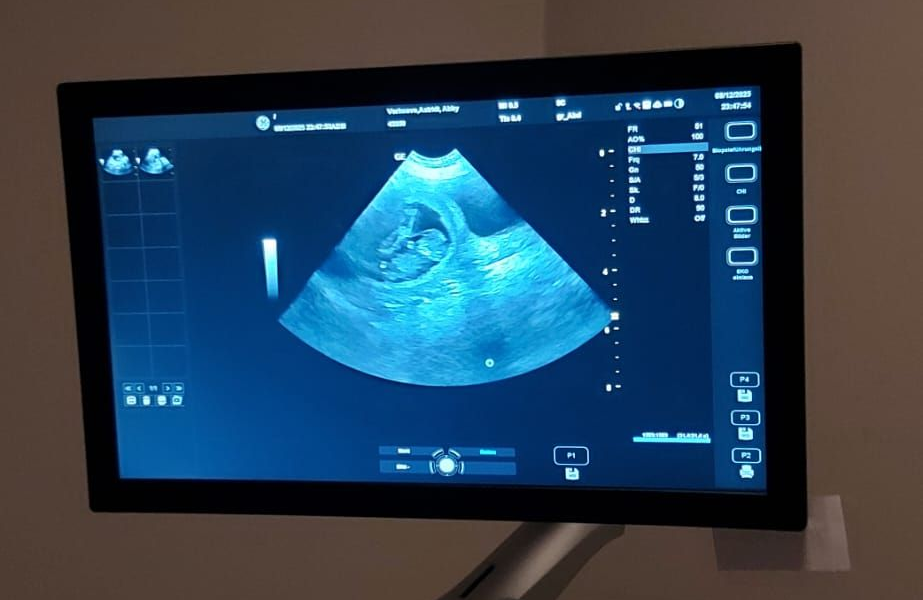

| 5 | 08.12.25 - 14.12.25 | 15,2 | Sehr Anhänglich - Isst schlecht - will nicht gerne raus | 08.12.25 - Ultraschall Feststellung Trächtigkeit |